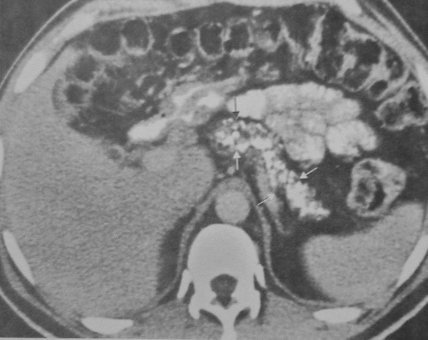

- Kontrastlı KT və ya MRT standart müayinədir, şişi və yayılma dərəcəsini müəyyənləşdirilməsində önəmlidir.

- Görüntüləmdə: erkən arterial fazada contrast tutan və venoz fazada yuyulan, MRT-də hipointens, ətraf toxumalara invaziv, böyüməyə meylli, baş nahiyyəsində yerləşərək xoledoxu və pankreatik axacağı genişləndirən (“iki axacaq simptomu”) törəmə

- Kontrastlı KT və ya MRT ilə pankreasda kütlə təyin İnsulinomalardan fərqli olaraq qlükaqonomalar böyük ölçülü olurlar və tapılması çətinlik törətmir. Adətən cisim və quyruq nahiyyəsində yerləşirlər.